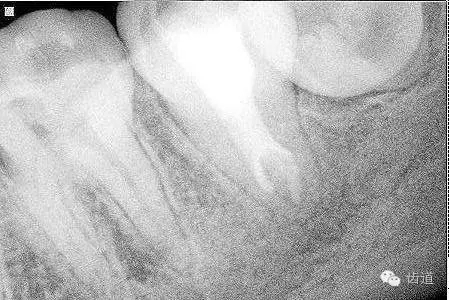

2. 術(shù)前X片

可見37根管影像清晰,根中上三分之二粗大,根尖三分一分為近遠(yuǎn)中兩根管,形態(tài)均呈弧形,根尖周膜連續(xù)性中斷,根尖周透射影明顯

2. 術(shù)后半年X線檢查,可見根尖周膜連續(xù)性恢復(fù),根尖周透射影消失